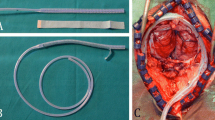

Figure 1 shows a schematic of the experimental apparatus. Bleeding models were created by perforating the center of a simulated blood vessel (Toughsilon TSG-A10; TANAC, Gifu, Japan) with an inner and outer diameter of 4 and 6 mm, respectively and a length of 50 mm using a syringe needle. The effect of wound size was examined by defining it as significant when perforated with an 18-gauge needle and small when perforated with a 27-gauge needle. A glass syringe (Tsubasa Industry, Tokyo, Japan) and the bleeding models were connected using Tygon tubes (Yamato Scientific) with an inner diameter of 4 mm. A blood pressure transducer (DX-100; Nihon Kohden, Tokyo, Japan) was connected to the bleeding model to monitor the intravascular pressure. The blood pressure transducer was connected to a strain amplifier (CDV-700A; KYOWA ELECTRONIC INSTRUMENTS, Tokyo, Japan), and the output voltage from the strain amplifier was input into a load-testing machine (AUTOGRAPH AGS-X; SHIMADZU, Kyoto, Japan) via an input-output interface (SENSOR I/O EXTENSION BOX; SHIMADZU) and recorded using a load-testing machine control application (TRAPEZIUMX; SHIMADZU). Glass syringes, Tygon tubes, bleeding vessel models, and blood pressure transducers were filled with an iodine contrast medium (Omnipaque; GE Healthcare, Japan) or CO2. Tygon tubes and bleeding models were fixed at the bottom of a 37 °C thermostatic bath to account for changes in viscosity with temperature. The height of the water surface was fixed at 8 cm, assuming an intra-abdominal pressure. Iodine or CO2 contrast media were injected into the bleeding models using a load tester to maintain the piston of the glass syringe at a constant speed and flow rate. An experimental system was created in which the perforation of the bleeding model was the only exit from the contrast-filled circuit.

Schematic diagram of the experimental apparatus. The simulated blood vessels with large and small wounds were connected to glass syringes using TYGON tubes. A bleeding model and blood pressure transducer were used to monitor the blood pressure. The output voltage from the strain amplifier was transferred to the load tester via an input/output interface and recorded using the load tester control application. All circuits were filled with iodine contrast medium or CO2. A glass syringe was placed on the autograph to measure the pressure when CO2 or iodine contrast medium leaked from the simulated blood vessel